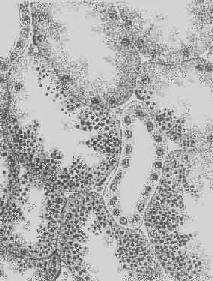

5.淀粉样变性 组织内有淀粉样物质沉积称为淀粉样变性(amyloid degeneration,amyloidosis)。淀粉样物质为一种结合粘多糖的蛋白质,遇碘时被染成赤褐色,再加以硫酸则呈蓝色,与淀粉遇碘时的反应相似,故称之为淀粉样物质。此物质常浸润于细胞间或沉积于小血管的基底膜下,或沿网状纤维支架分布(图1-22)。淀粉样物质在HE染色切片中为淡红色均质状,电镜下则为纤细的丝状。

图1-22 肝淀粉样变

>淀粉样物质呈均质状,沉着于窦内皮下,肝细胞索受压萎缩×150